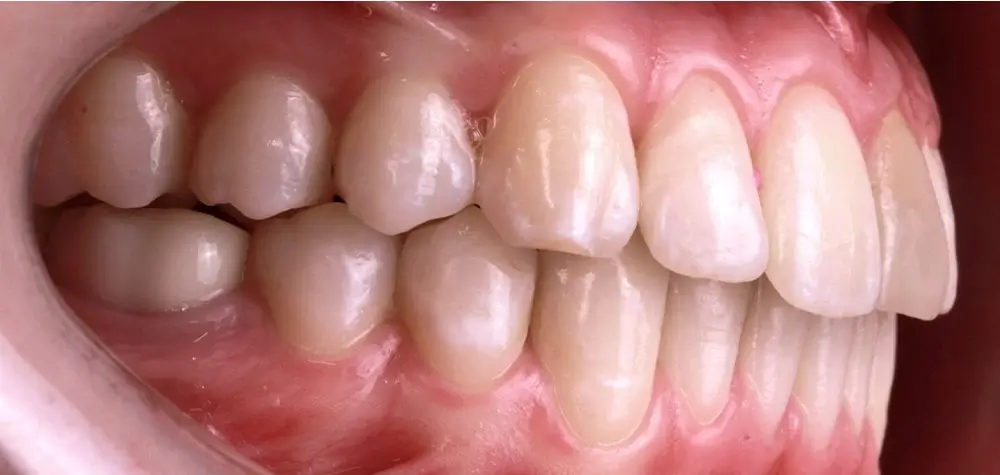

Кейс 9

Бирковская Екатерина Александровна

Количество кап ВЧ 23

Количество кап НЧ 23

ДО

ПОСЛЕ